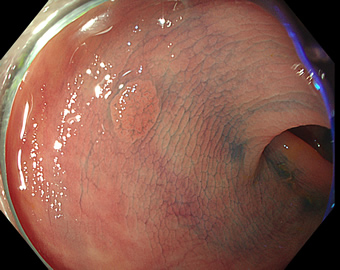

特に、下のような「Ub型(全く凸凹の無い完全に平坦な病変)」は、以前は「ほとんど見つからなかった」のが、TXIを使うようになってから「日常的に」見つかるようになりました。

通常観察 TXIモード

青い色素は追加していません![]()